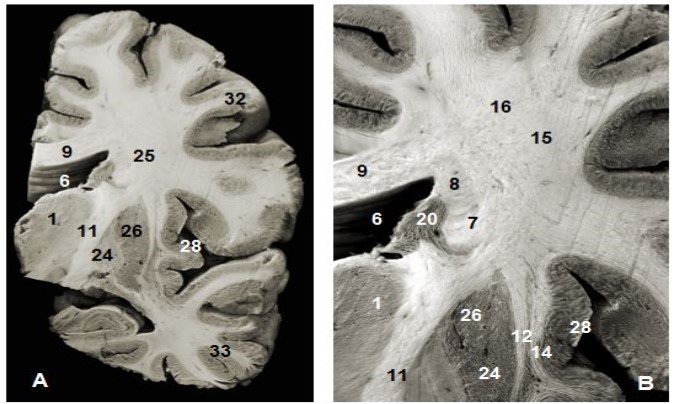

Figure 1.(A) Coronal view of the left hemisphere and (B) global view after magnification and before dissection of (A). 1. Thalamus, 6. Lateral ventricule 7. Subependymal substratum, 9. Corpus callosum, 11. Internal capsule, 12. External capsule, 13. Claustrum, 14. Extreme capsule, 16. Upper branch of the SLF , 20. Head of caudeus nucleus, 23. Putamen, 24. Globus pallidus, 25. Lower branch of SLF 28. Insula, 30. Corona radiata, 32. Parietal pole, 33. Temporal pole.

(A) Coronal view of the left hemisphere and (B) global view after magnification and before dissection of (A). 1. Thalamus, 6. Lateral ventricule 7. Subependymal substratum, 9. Corpus callosum, 11. Internal capsule, 12. External capsule, 13. Claustrum, 14. Extreme capsule, 16. Upper branch of the SLF , 20. Head of caudeus nucleus, 23. Putamen, 24. Globus pallidus, 25. Lower branch of SLF 28. Insula, 30. Corona radiata, 32. Parietal pole, 33. Temporal pole.

Anterior and superior thalamocortical pathways course obliquely and connect anterior, mediodorsal, lateral ventral anterior, lateral dorsal and lateral posterior thalamic nuclei to the cerebral cortex. They exposed after the removal of the head and body of the corpus callosum were . A coronal view of the thalamus confirms the course of these fibers to the thalamus. The sub-ependymal stratum and gray matter are medial to the thalamic radiations (Figure 1). The successive excision of the insular cortex, claustrum, fibers of the extreme capsule, the putamen and globus pallidus and pyramidal tract exposed other components lateral to the internal capsule (Figure 1, Figure 4). Fibers of the extreme and external capsules and of the lenticular nucleus (putamen and globus pallidus) formed an inferior relationship with the stem of the uncinate and the inferior occipitofrontal fasciculi. A coronal section through the cerebral hemisphere and the thalamus completed the study of thalamic radiations. The optic radiations and the ventral amygdaloid tract which loop through the anterior perforated substance and the lateral expansion of the anterior commissure sheathed by the Gratiolet canal, which were not include intentionally in our illustrations, were further away. Gratiolet optic radiations connect the thalamus to the geniculate body and the posterior nucleus of the occipital cortex. These thalamic radiations line up the lateral ventricle.